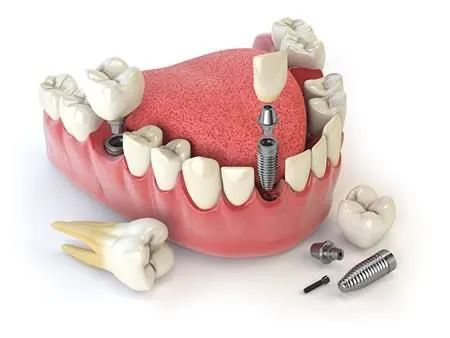

种植牙模拟真牙结构,通过在牙槽骨中植入种植体进行稳固,然后在基台上安装坚固美观的牙冠,让缺牙重生,是目前修复缺失牙齿最好的方法。

简单来说,种植牙就像重新栽树,原来的树没有了,我们就重新在原来的地方栽一棵,但因为这颗树是人造的,根不会长,所以我们就要一次性把人工的树根弄的牢固,在牙槽骨(土壤)里打好地基,只要树根弄的好,支撑、受力这些都没问题,然后再装上外边的底座跟牙冠,就算种植成功了。

种植牙中最关键的就是人工牙根和本身牙槽骨的结合!影响这个成功的要素很多,例如植入是否精准,牙根材料跟骨头的结合性好坏,种植医生的技术等等,所以,你在做种植牙时要盯住这些,你的种植牙就不会有出大错,当然,水平差的医生最怕你盯着这些。